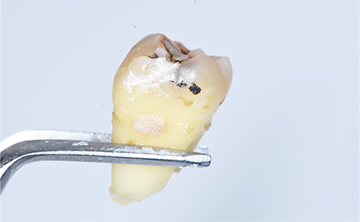

虫歯を放置した場合の抜歯後の歯の写真

最終的にそれでも放置しておくと膿がどんどん溜まっていくので、顔や首などが腫れ上がってしまい発熱が続き最終的には、救急に運ばれて切開排膿することになります。

虫歯になってしまった抜歯後の歯の写真